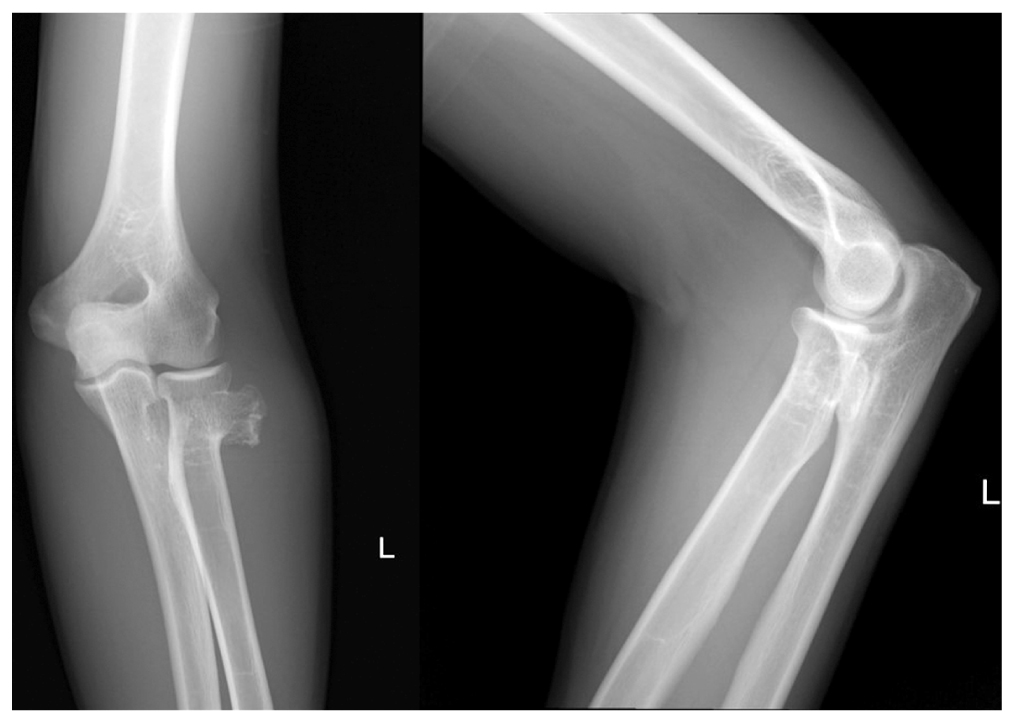

По данным рентгенографии локтевого сустава визуализируется новообразование в области шейки лучевой кости (рис. 2). Для уточнения характера новообразования и его отношения с параартикулярными структурами принято решение о выполнении компьютерной (КТ) и магнитно-резонансной (МРТ) томографии локтевого сустава.

Рис. 2. Рентгенограммы левого локтевого сустава в прямой переднезадней и боковой проекциях: визуализируется новообразование костной плотности в области шейки лучевой кости

Fig. 2. An X-ray image of the left elbow joint in the antero-posteral and lateral views: a bone density formation is visualized in the area of the radial neck